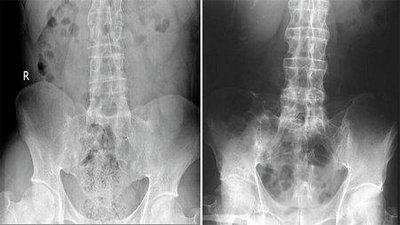

(图:X线片显示其双侧骶髂关节不规则变窄)

检查结果:白细胞偏多,血沉及C反应蛋白显著偏高,HLA—B27检查呈阳性,免疫球蛋白升高,类风湿因子阴性。骶髂关节X线片显示其双侧骶髂关节软骨下骨出现骨硬化、骨质增生、关节间隙变窄症状,脊柱X线片显示异常。

(图:脊柱治疗前后对比图)